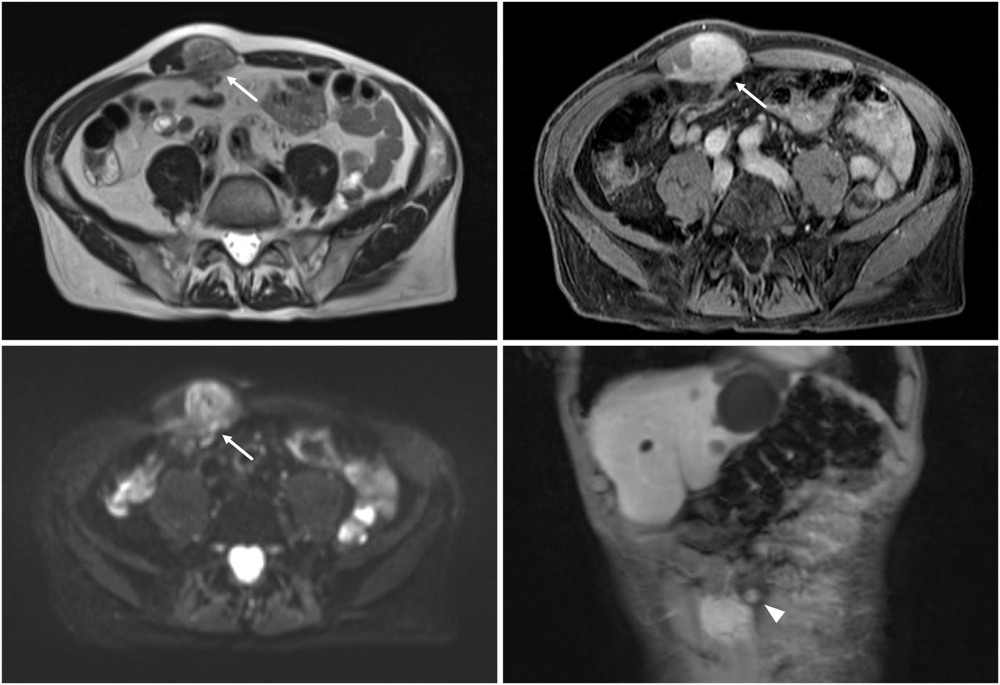

影像学检查:腹部超声示右侧腹直肌内见一大小约 6 cm × 3 cm × 3 cm 均质肿块。磁共振成像显示腹直肌鞘内一梭形病变,呈强化及弥散受限,浸润邻近腹壁,并可能累及腹横筋膜。病变与横结肠及小肠毗邻,疑有腹腔内蔓延(图 1 右下示病变邻近脐部)。腹腔内未见其他异常,仅见多发肝囊肿

图 1:疑似软组织肿瘤的磁共振成像(左上为 T2 加权横切面;左下为弥散加权横切面;右上、右下分别为钆剂增强 T1 加权横切面和冠状切面)